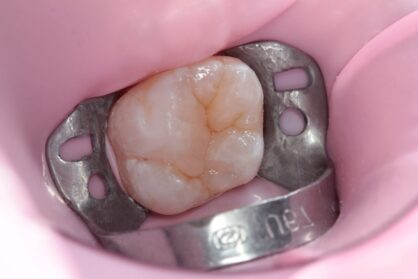

Приклади робіт лікаря-стоматолога

Естетична реставрація. До / після

Сучасні композиційні матеріали для реставрацій ідеально відновлюють естетику зубного ряду. Лікар підбирає прозорість та відтінок матеріалу аби пролікований зуб не відрізнявся від сусідніх здорових.